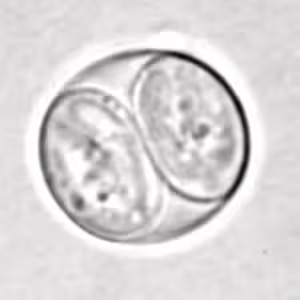

Toxoplasma gondii sporulated oocyst.

Toxoplasma gondii unsporulated oocysts.